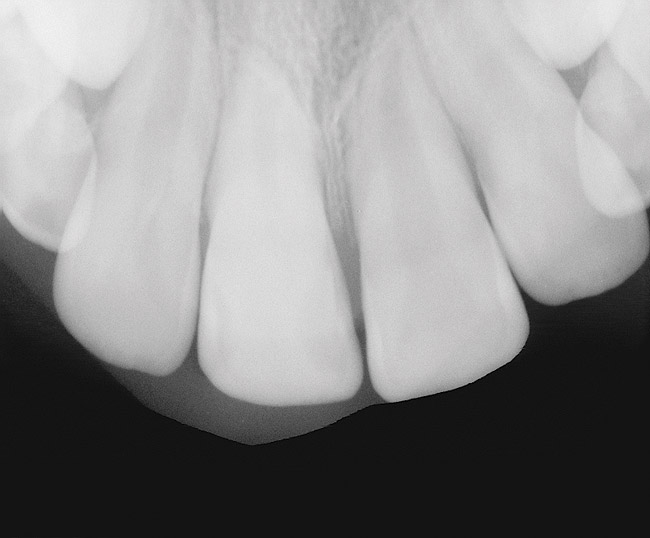

Figure 6  Root resorption secondary to orthodontic tooth movement.

Figure 6